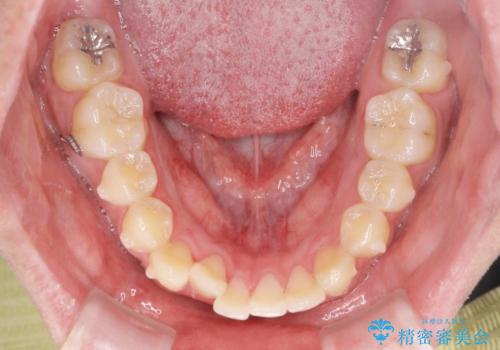

- ワイヤー矯正 → インビザライン

- 3年

見た目、噛み合わせが大きく改善し、大変喜んでいただくことができました。